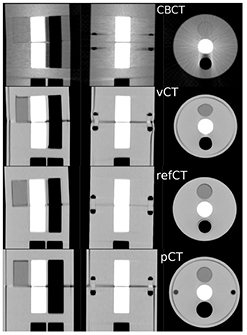

3.1. Registration

Figure 2 presents the pCTCBCT in planning configuration, the refCTCBCT and CBCTCBCT in treatment day configuration as well as the vCTCBCT resulting from DIR of the pCT to the CBCT. Figure 2 shows the difference in phantom diameter, angle and airway diameter between the treatment day configuration and the planning configuration. We observe that the vCTCBCT diameter has been reduced; however the air gap between the phantom body and fat ring caused by an imperfect fit has not been eliminated by the DIR. The reverse situation was observed in the airway where the refCTCBCT exhibits an air gap due to the imperfect fit of the airway sleeve which is not visible in the vCTCBCT. The agreement between the vCTCBCT and the refCTCBCT as well as the difference between the pCTCBCT and refCTCBCT are better visualized in the checkerboard representation of figure 3. There is good agreement between vCTCBCT and refCTCBCT for the phantom outer contour, airways and vertebral column. However the muscle insert in the vCTCBCT has been distorted, most likely due to the low CT number contrast between this insert and PMMA. It is questionable whether this situation would arise in a patient geometry given the higher number of gradients found in those images. The distortion of the muscle insert raises questions as to the use of the deformation fields to accumulate dose in a reference time point such as the pCT. However an investigation of dose accumulation was beyond the scope of this paper. We observed a misalignment in the Z direction resulting from the rigid deformation of the pCT to the CBCT. This misalignment is of the order of the slice thickness and could be due to the different geometries being aligned. While manual correction of this misalignment is straightforward this was not done as we aimed at evaluating the complete automatic workflow. Furthermore, the DIR performed following rigid registration corrects for residual shifts.

Figure 2. CT scans of the phantom in treatment day configuration (CBCTCBCT, refCTCBCT) and in planning configuration (pCTCBCT). The vCTCBCT is the result of DIR of the pCT to the CBCT.

Standard image High-resolution imageFigure 3. (a)–(c) Checkerboard comparison of the pCTCBCT and refCTCBCT. (d)–(f) Comparison of the vCTCBCT and refCTCBCT.